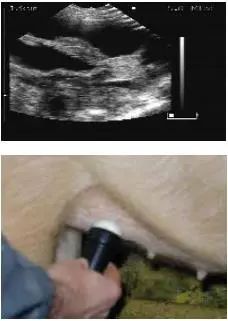

2.4 不同位置的扫描影像图

用B超进行妊娠鉴定时,应检测母猪身体的不同部位,以获得子宫内的详细情况,不同位置的扫描影像见图1、图2、图3、图4和图5。

图 1 位置1超声波影像图